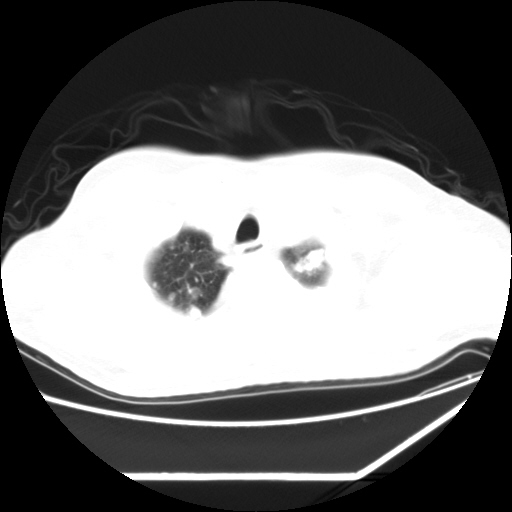

男,57,畏寒,发热

两肺野多发大小不一高密度灶,纵膈内见肿大淋巴结,要考虑转移瘤可能。双侧胸腔少量积液。

双肺多发结节样病灶,部分内见透光区,纵隔内见淋巴结肿大。结核临床如有畏寒,高热,白细胞增高首先考虑迁徙性肺脓肿(多是金黄色葡萄球菌感染)。

注意除外转移瘤。

1)考虑两肺感染性病变(金黄色葡萄球菌肺炎?);建议抗炎治疗后复查排除其他。2)双侧少量胸腔积液。